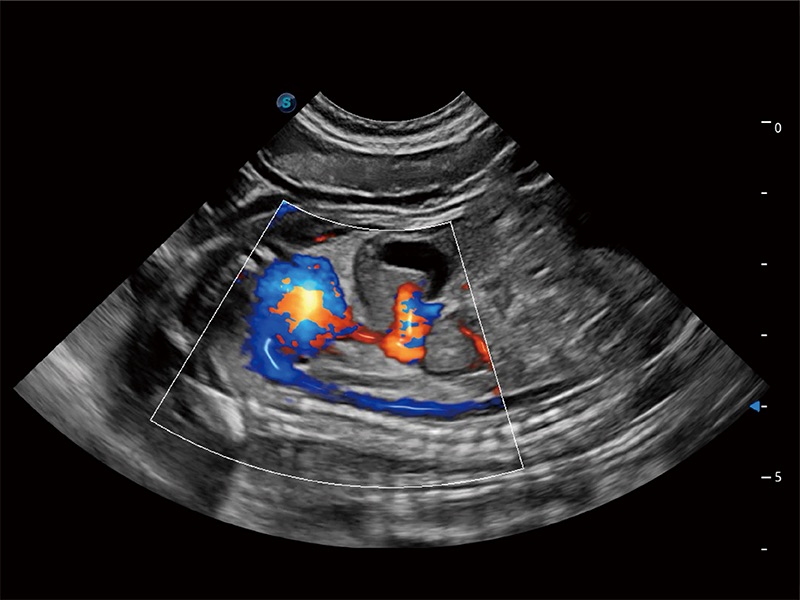

极大提升超低速微细血流的检出能力,同时更精准地滤除软组织和超声信号,为兽用医生提供以往无法通过常规血流获得的疾病诊断信息。

在传统二维血流成像的基础上,呈现血流的立体感,具有动感的生命力之美。即便是微小的血管也能轻松应对,提高了血流的视觉敏感性。

ProPet 80 配备了丰富的心脏探头群、先进的成像技术和专业的心脏测量工具,可帮助动物医生为不同体型和生理结构的动物提供心脏和心肌功能的全面评估。